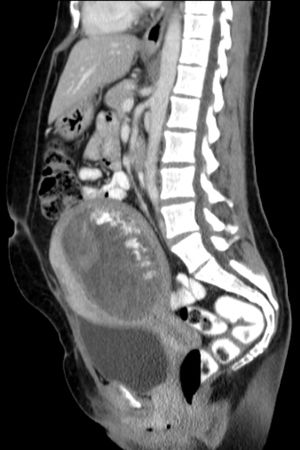

Hydatidiform mole on CT, sagittal view